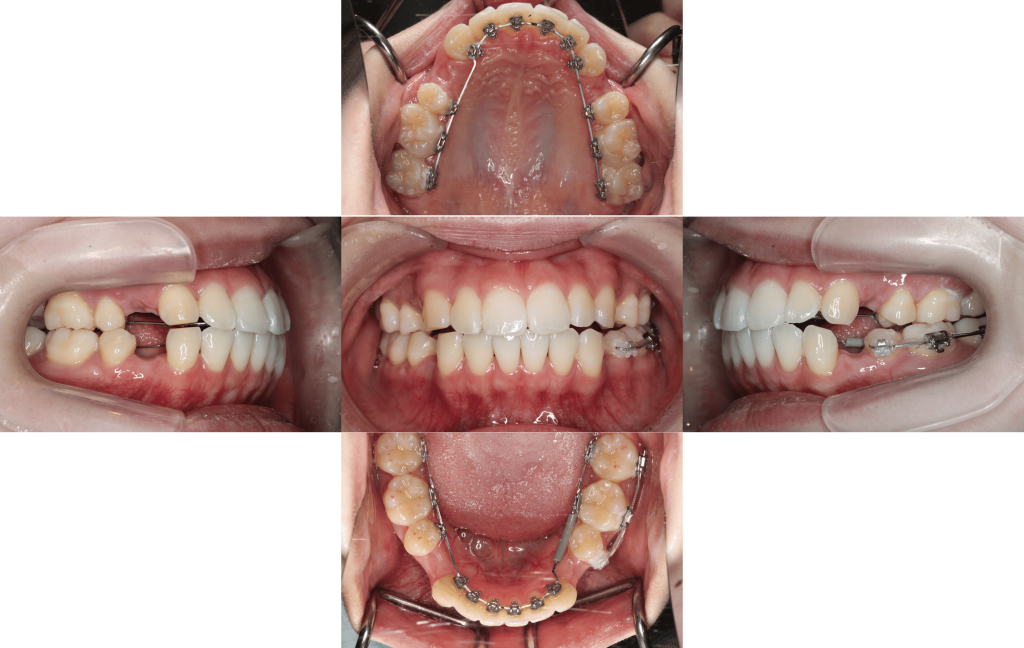

約6か月経過